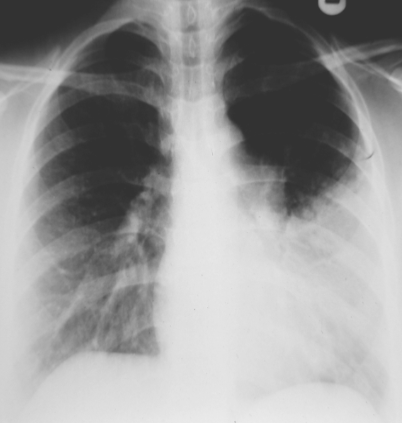

Silhouette sign: In this case the left border of the heart is not visible.

Due: Pneumonia/pleural effusion